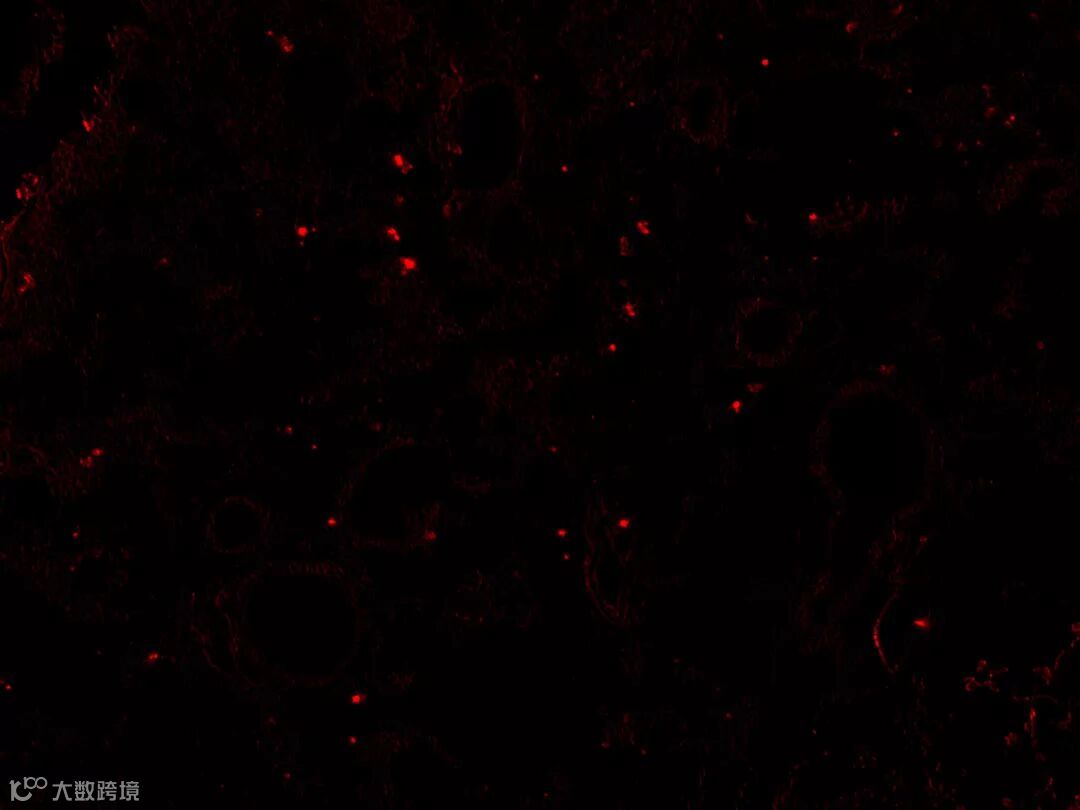

另外,中源协和与天津市海河医院共同申报的2018年天津市重大疾病防治科技重大专项项目《hUC-MSC干预特发性肺纤维化的治疗技术研究》,临床前研究获得政府资助。根据动物实验的最新结果,人源脐带MSC经荧光标记后通过尾静脉注射到造模小鼠体内,可在肺组织中清晰见到标记的MSCs,并起到良好的逆转肺纤维化的治疗作用。

(动物实验新结果照片)